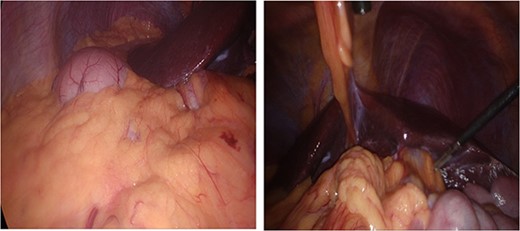

Dissection started with separation of omental adhesions from the fundus of the gallbladder. This was done using a combination of hook diathermy and blunt dissection techniques. Once these adhesions were taken down, Calot’s triangle was identified. Anatomical cross check was performed as usual by identifying segment IV of the liver, Hilar plate, and the hepatic pedicle. Dissection was kept lateral to the ‘line of safety’ and well above Rouviere’s sulcus. The operating surgeon used their right hand for the majority of dissection of Calot’s triangle as usual. Once Calot’s triangle was dissected, two structures were identified going into and out of the gallbladder, and Strasburg’s ‘critical view of safety’ (Fig. 4) was seen [4, 5]. The cystic duct and cystic artery were clipped with three 10 mm endoscopic haemostatic clips and ligated. The 10 mm ligaclipper was inserted through the subxiphoid port and placement of clips was controlled using the surgeon’s left hand. The gallbladder was then dissected from the gallbladder fossa and removed via the umbilical port in a Bert bag.

Critical view of safety with plane of dissection lateral to line of safety; two structures are viewed both entering the gallbladder and the lower border of the gallbladder dissected from the liver.

According to Orozakunov et al, surgeons should be comfortable with the anatomy before dissection and recognize that in SIT, the anatomy is a mirror image [7]. As mentioned in this case, the surgeon performed anatomy checkpoints, which were key to safely performing this case. Before clipping the structures, we ensured that Strasburg’s ‘critical view of safety’ was visible from both the medial and lateral aspects of Calot’s triangle (Fig. 4).